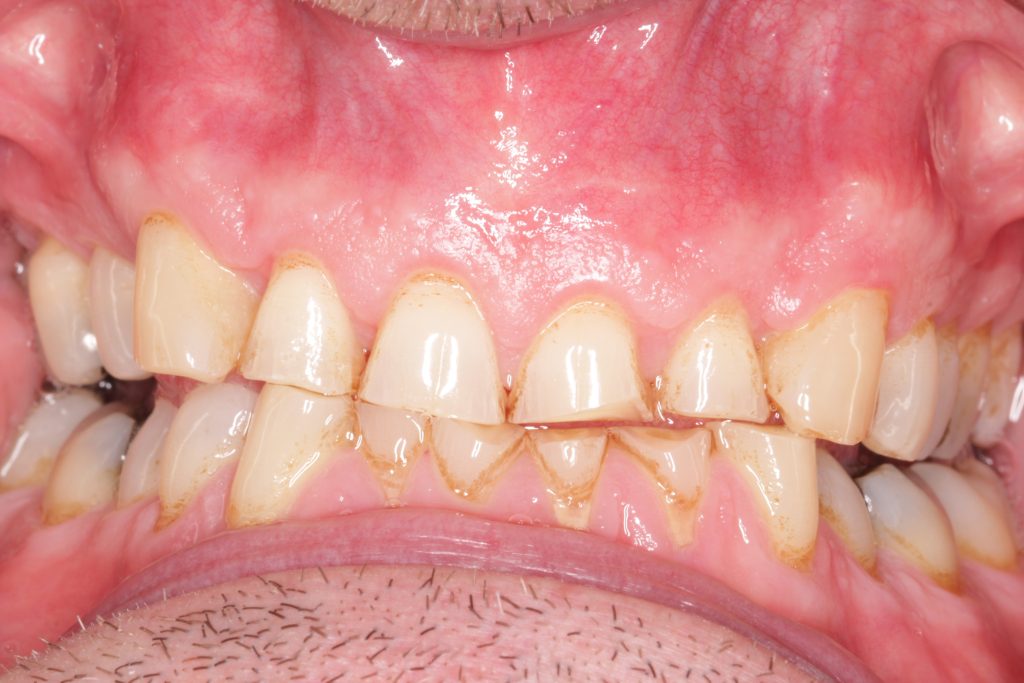

Initial presentation

A male 56-year-old presented with generalised tooth wear and has been a long-standing patient of the practice. He reported no pain or concerns until the extensive wear was highlighted in his examination.

He revealed that he has suffered nocturnal bruxism for many years and has noticed that his teeth have noticeably gotten shorter over the years believing that it was due to natural ‘wear and tear’.

Taking a patient-centred approach, we discussed and highlighted his teeth were at high risk of complete loss of clinical height and pulp involvement. If left unprotected and subsequently required extraction, there would be little room for implants or dentures owing to the alveolar compensation. Thus restoring the dentition in the patient’s later years would prove extremely challenging.

- Parafunction: evident in generalised tooth wear from nocturnal bruxism and hypertrophic masseters

Other challenges

- Alveolar compensation, maintaining occlusal vertical dimension (OVD)

- Shortened clinical crowns with pulp exposure imminent on lower anteriors

- Asymmetrical gingival zeniths

- Buccally positioned canines.